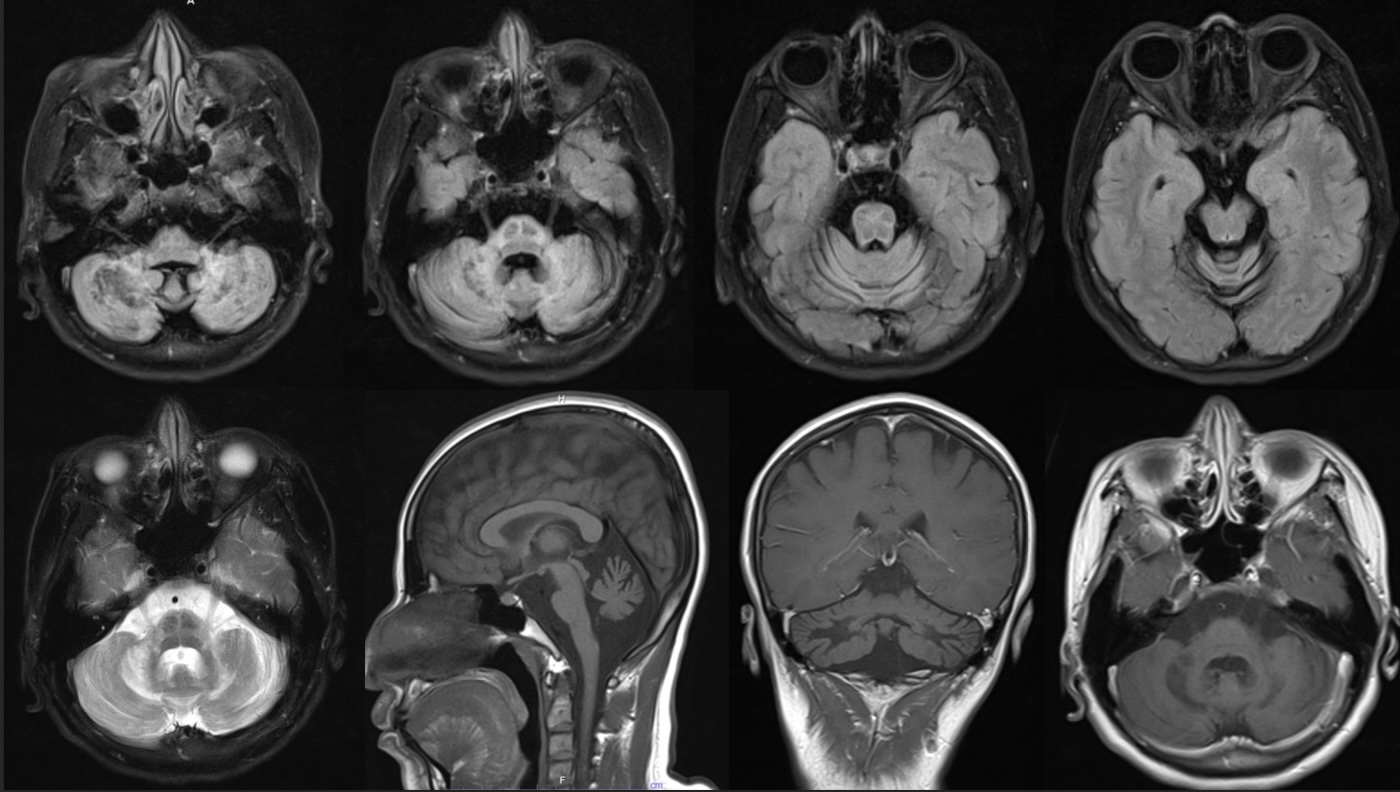

Results: Brain MRI revealed significant pontine and diffuse bilateral cerebellar atrophy associated with cruciform hyperintensity T2FLAIR in an atrophic area compatible with Olivopontocerebellar atrophy ( OPCA) and hot cross bun (HCB) sign. Blood test for autoimmune and paraneoplastic antibodies all were negative . Cerebrospinal fluid ( CSF) examination was normal but was limited for sending CSF HIV viral load and JC virus. Genetic testing was absent of repeated expansion for SCA 1,2,3 and SCA 17. According to history of one year non viral suppressed HIV disease prior to her clinical presentation, the diagnosis was HIV encephalopathy with olivopontocerebellar atrophy. This brainstem pathology interfere central to peripheral autonomic network of crying and explain of distress vocalization of non emotional pathological crying of her.

MRI brain of this patient with OPCA and HCB sign